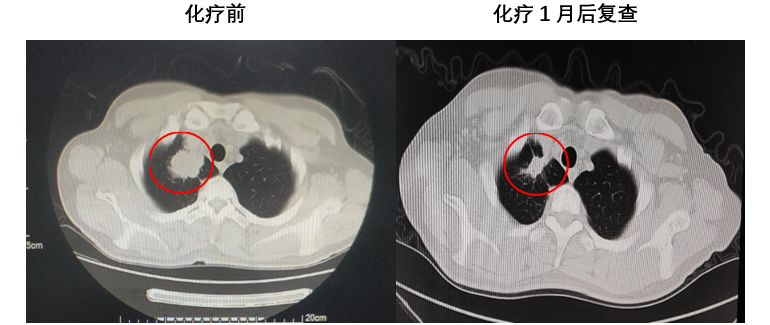

患者为46岁中年男性,主因前额搏动性疼痛1月余,加重1周至当地医院就诊,颅脑CT检查提示右侧颞顶叶占位:转移瘤?,入院完善相关术前检查后发现该患者肺部占位、颅内多发占位,怀疑肺癌脑转移瘤。 结合患者一般情况及影像学检查分析病情。认为颅内右侧颞顶叶肿瘤占位效应明显,导致中线移位,脑室受压,肿瘤进展较快,有进一步增大可能,严重时可能出现脑疝,危及生命。且该占位最大径>3cm,放化疗效果差,同时手术可明确肿瘤性质,因此计划手术切除右颞顶叶占位,其余颅内占位较小,占位效应不明显。肺部占位可在明确组织病理及分子病理后再行治疗。 颅脑磁共振提示颅内多发占位 胸部CT提示右上肺尖段占位 排除绝对手术禁忌后于2021年11月10日行全麻下左侧卧位右侧颞顶叶占位切除术。术后患者病情平稳,未见新发神经功能障碍,查体同术前。术后病理提示:符合低分化腺癌,考虑为肺来源。免疫组化提示:CK7(+)、NapsinA(+)、TTF-1(+)、ALK(ventana)(-)、PD-L1(SP263)(30%)。分子病理提示:EGFR 19缺失突变。 术区CT 出院后患者至我院脑转移瘤多学科联合门诊拟定下一步诊疗方案。脑转移瘤MDT专家团队联合为转移瘤患者会诊,各学科专家详细询问了患者的相关病情及诊疗经过,并仔细阅读了影像学检查及实验室检验结果,从各自专业角度,结合患者整体病情,提出了各自相关专业的处理方案以及为患者制定了全面、精准、规范的诊疗计划: 神经外科冯世宇主任:患者脑转移瘤术后恢复良好,建议下一步综合治疗。 放射科肖华锋主任:阅患者术前MRI和术后CT提示颅内多发转移瘤,右侧颞顶叶转移瘤术后改变。肺部CT提示右上肺肺癌,建议肺部CT增强扫描,颅脑MR增强扫描,定期复查。 胸外科马永富主任:病史已阅,建议完善胸部增强CT。评价右上肺手术机会。 肿瘤内科吴志勇主任:肺癌脑转移考虑EGFR作为主要驱动基因治疗,结合TP53/ target=_blank class=infotextkey>P53突变,建议应用EGFT TKI+安罗替尼治疗,EGFT TKI首选奥希替尼。 综合意见: 患者就诊联合门诊后积极行化学药物治疗(奥希替尼,口服 80mg 1/日;安罗替尼 口服 8mg 1/日),近日再次至我院复查颅脑磁共振提示病情控制良好(如图)。 右颞顶占位 其余多发占位 肺部占位 病例总结 该患者为46岁中年男性,主因头部疼痛发现颅内多发及肺部占位,高度怀疑肺癌脑转移,但肿瘤性质未明确;颅内右侧颞顶叶肿瘤占位效应明显;肿瘤直径>3cm,放化疗治疗效果较差并且存在风险。手术可快速解除颅内高压症状,消除病灶对周围脑组织的压迫,并且明确肿瘤性质,根据组织病理及分子病理能够寻找肿瘤相关突变基因靶点药物。因此采取了手术切除颅内右侧颞顶叶肿瘤,缓解了占位效应,明确了肿瘤组织病理及分子病理,为患者赢得了下一步综合治疗的时间。 该病例的启示 颅内转移瘤是否手术应进行综合评估,其中包括肿瘤的数量、大小、性质、部位、患者一般情况等。 1、 颅内单发肿瘤最大径>3cm,水肿范围大、占位效应明显时应行手术切除,及时进行减压,挽救患者生命;但其病理性质明确,且对放化疗敏感时,可不首选手术治疗。 2、 颅内多发,若肿瘤数目≤3个,且能完全切除者可行手术治疗;若肿瘤>3个,则建议行放疗、化疗等非手术治疗。但是若占位效应明显、出现梗阻性脑积水、肿瘤卒中甚至脑疝等情况时应行手术切除较大占位病变以达到减压目的,患者赢得下一步治疗的时间以后,再根据组织病理和分子病理,进行化疗或靶向治疗或者放疗等综合治疗。 3、 若肿瘤性质不明确者,应行手术切除或穿刺活检明确组织病理及分子病理,根据其结果可寻找有效的化疗药物或靶向药物等综合治疗的方案。 4、 肿瘤部位较深或位于功能区(如脑干、基底节区、丘脑),评估手术风险高可能带来不可逆的功能障碍,一般不首选手术,可先选择放疗或化疗。 解放军总医院第一医学中心脑转移瘤联合会诊团队由神经外科、肿瘤科、放疗科、放射科、胸外科、乳腺外科等科室专家组成的专家团队,各相关学科专家结合患者的具体情况,制定出最合适患者的个性化的精准治疗方案,提高患者的治疗效果、生活质量以及生存时间。简要病史

术前影像